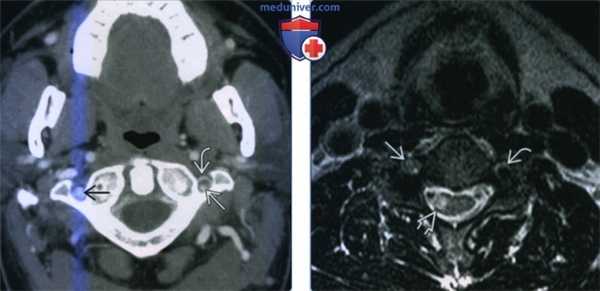

(Слева) КТ-ангиография, аксиальная проекция. Кольцо накопления контраста вокруг левой позвоночной артерии, в стенке сосуда отмечается небольшая гематома пониженной плотности. Просвет сосуда сужен, заполнен контрастом. Небольшой участок затемнения справа, как оказалось, не является следствием расслоения.

(Справа) MPT Т2ВИ, аксиальная проекция, другой пациент, получивший травму шеи и переломы шейного отдела позвоночника. Определяется травматическое расслоение правой позвоночной артерии: сравните ее с левой артерией, сигнал от которой отсутствует. Отмечается участок гиперинтенсивною сигнала в правой половине спинною мозга, который соответствует очагу инфаркта.